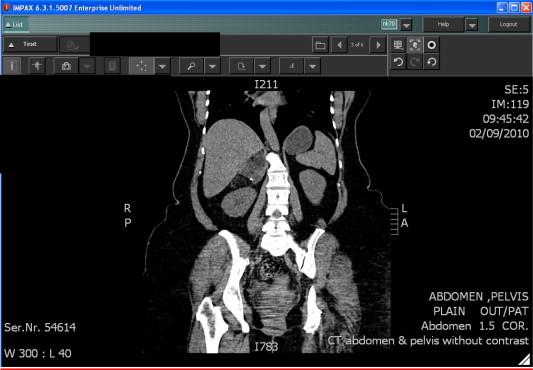

We reviewed 45 articles, that confirmed, with a high level of evidence-based medicine, that the diagnosis of a lipomatous adrenal tumour is made by various imaging procedures, particularly computed tomography (CT). We emphasise the importance to their management of the initial size of the adrenal mass, its increase in size over time, in addition to the presence of symptoms.

Lipomatous tumours of the adrenals are most frequently benign. The diagnosis is usually made by various techniques, in particular CT. The fundamental characteristics indicating the necessity of surgical intervention are the symptoms presented, volume of the tumoral mass (>5 cm), and the increase in size of the tumour as shown in two consecutive imaging studies.

我们回顾了45篇文章,这些文章以高水平的循证医学证实,肾上腺脂肪瘤的诊断可通过多种影像学检查,尤其是计算机断层扫描(CT)。我们强调肾上腺肿块的初始大小、其随时间的增大以及症状的存在对其治疗的重要性。

肾上腺脂肪瘤大多为良性。诊断通常通过多种技术,尤其是CT做出。表明需要手术干预的基本特征是出现的症状、肿瘤肿块的大小(>5厘米)以及连续两次影像学检查显示的肿瘤增大。